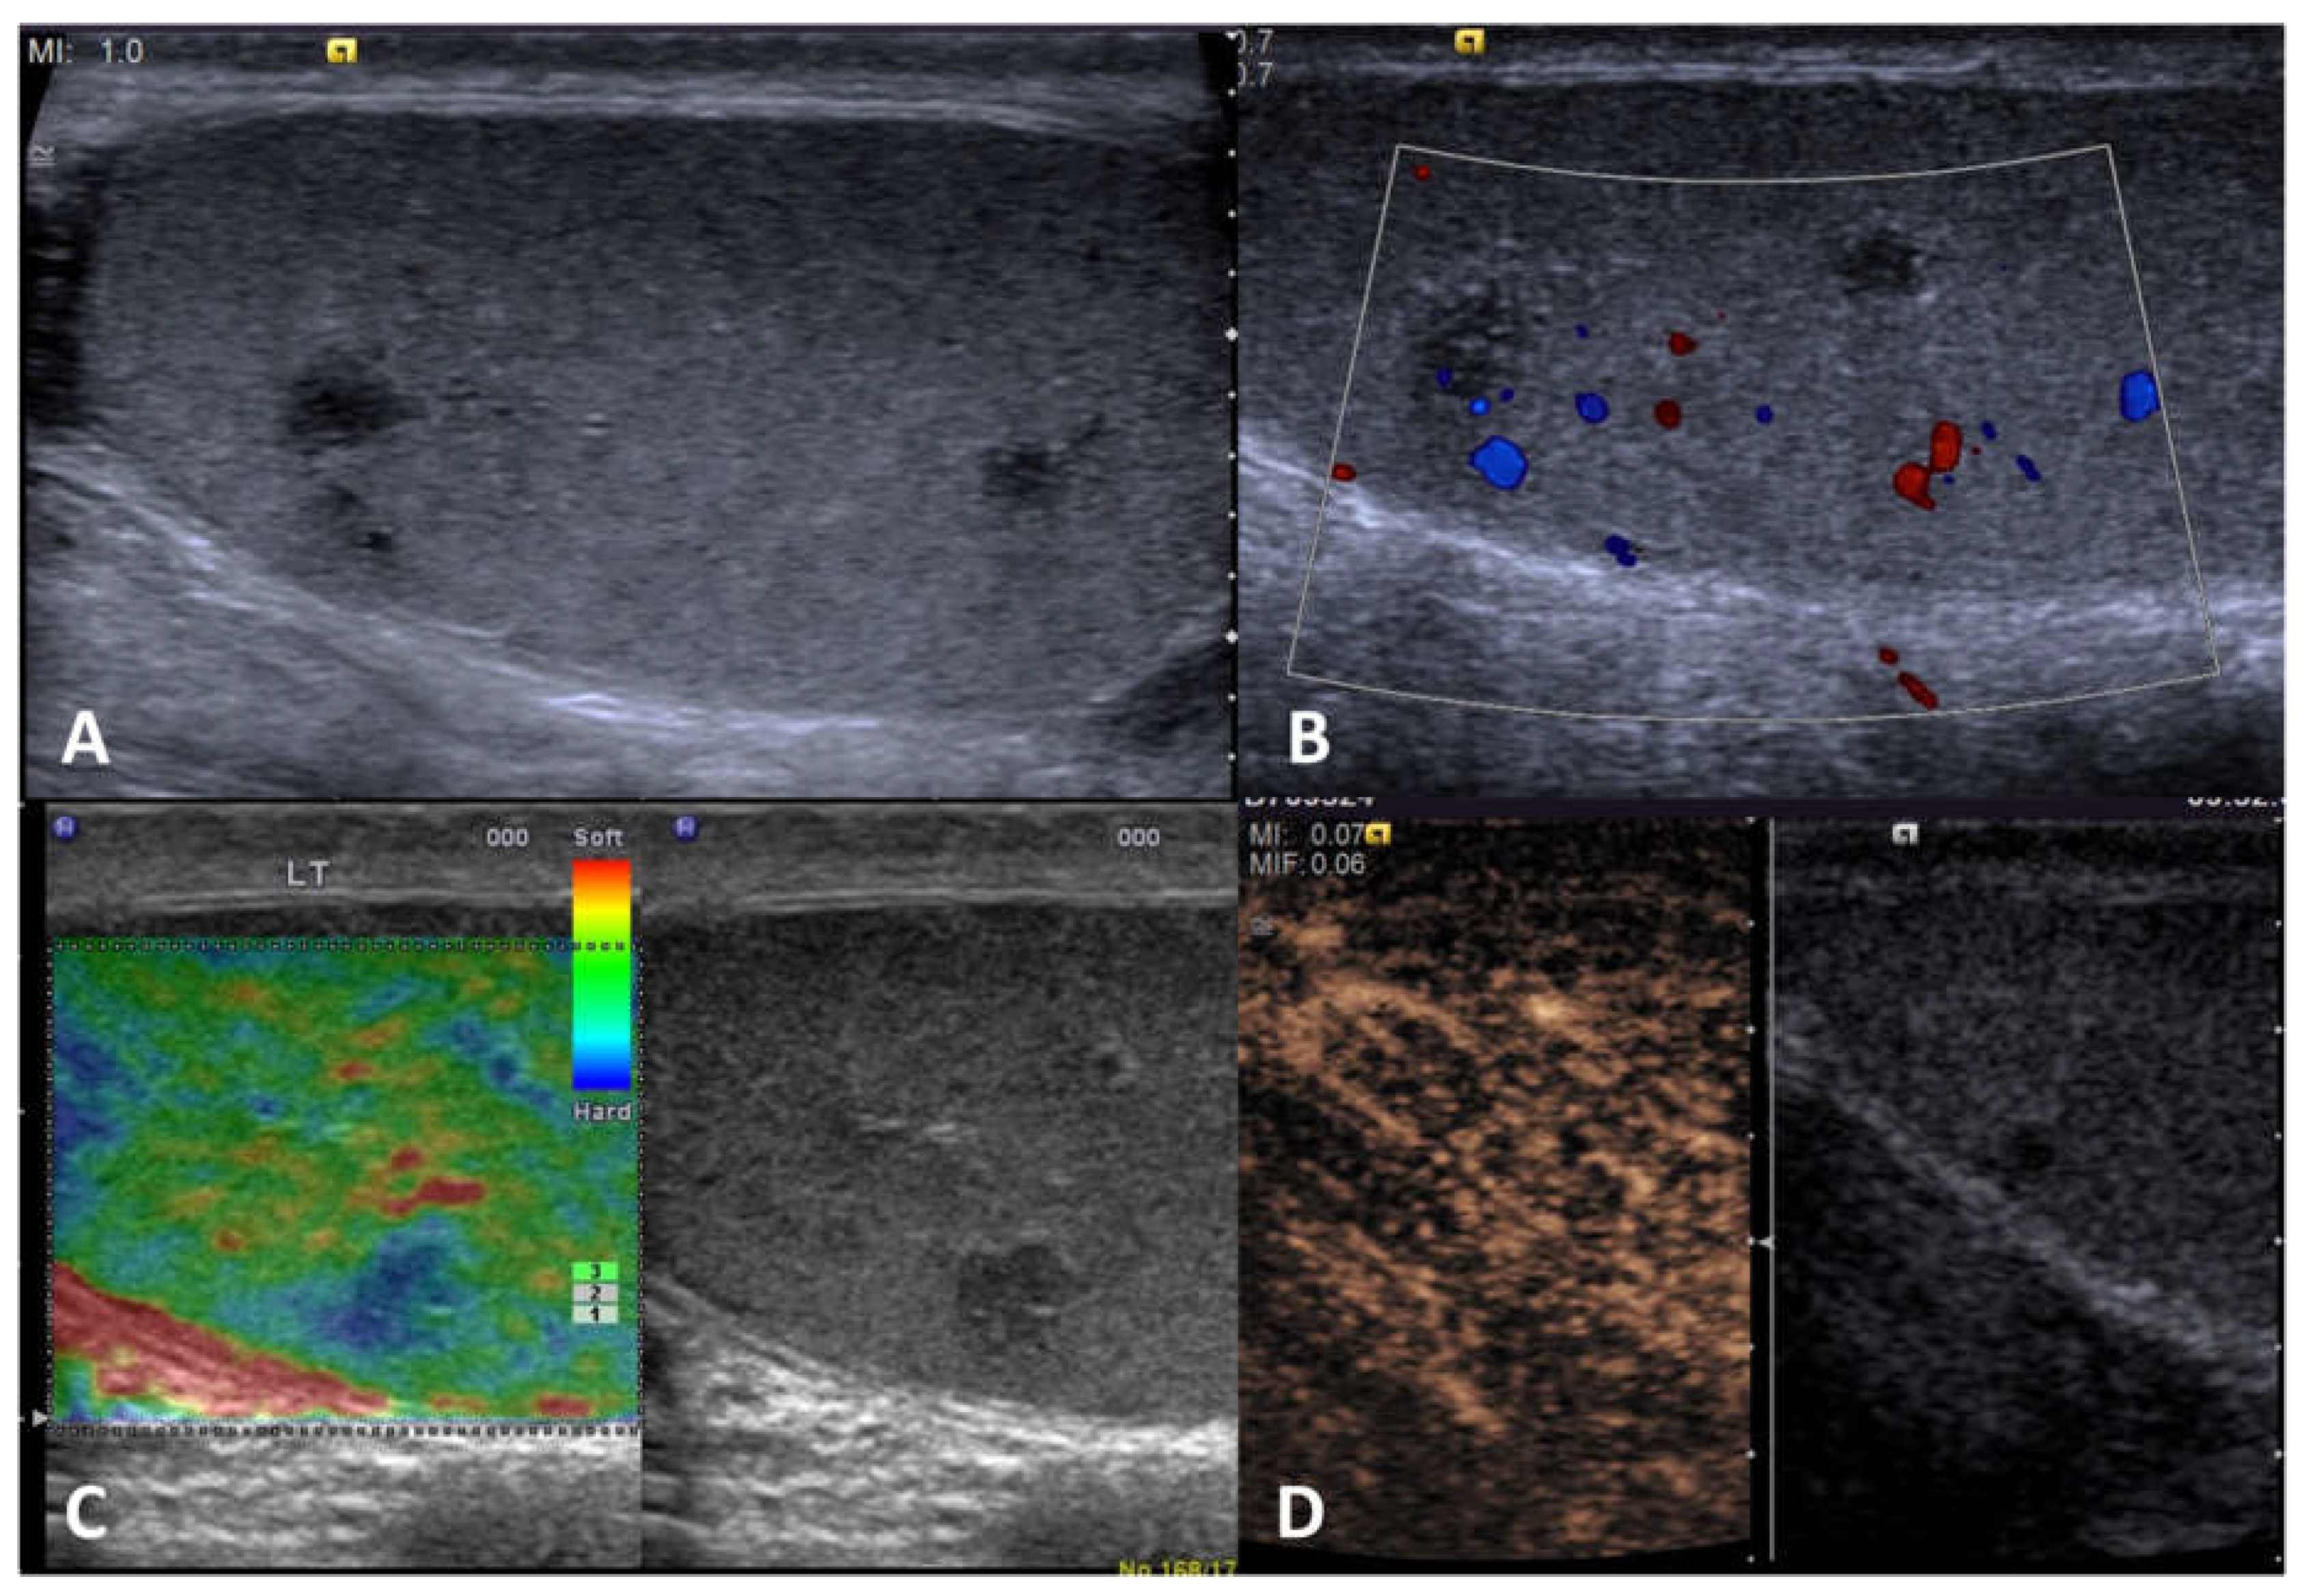

| Non-neoplastic intratesticular lesions | |||||

|---|---|---|---|---|---|

| Clinical presentation | GSUS | CDUS | CEUS | SE | |

| Sarcoidosis | in the context of a mulsystem disease; granulomas in other organs; asymptomatic OR painless/painful mass | hypoechoic lesions with irregular margins, often bilateral | possible signs of internal vascularization |

hypoenhanced | hard lesions with low/absent elastic strain |

| Segmental infarction | idiopathic or consequent to surgery, inflammatory events, blood disorders or autoimmune diseases; usually acute painful swollen scrotum (but also asymptomatic cases) | hypoechoic wedge-shaped or roundish area | Avascular or peripheral rim of low CD |

unenhanced/ perilesional rim enhancement |

soft lesions with high elastic strain |